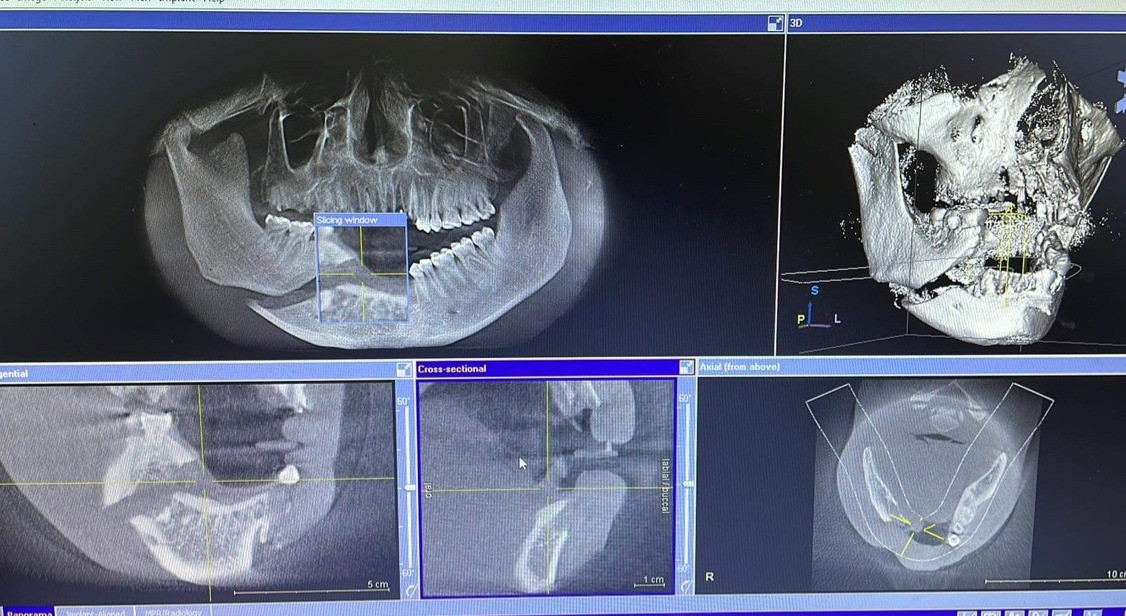

Theo Vietnamnet, 1 nam thanh niên 26 tuổi được đưa đến sơ cứu tại một cơ sở y tế trước khi đến Bệnh viện Hữu nghị Việt Nam - Cu Ba (Hà Nội). Bác sĩ Hoàng Phong Mỹ, Trưởng Khoa phẫu thuật hàm mặt, cho biết bệnh nhân được chẩn đoán vỡ nát xương hàm dưới phải, vỡ xương ổ răng hàm trên, dưới vùng cửa, mất toàn bộ răng cửa trên và dưới.

Bệnh nhân đã được phẫu thuật cấp cứu sau đó. Giữa tuần trước, bệnh nhân quay trở lại bệnh viện để trồng implant để có thể ăn nhai bình thường.